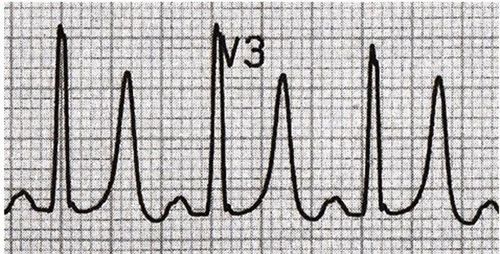

Điện tâm đồ (ECG - Electrocardiogram) là đồ thị ghi lại những thay đổi của dòng điện trong quả tim con người trên một đơn vị thời gian. Tim co bóp theo nhịp là nhờ vào sự điều khiển của một hệ thống dẫn truyền điện học của cơ tim. Dòng điện của tim tuy nhỏ, chỉ một phần nghìn volt nhưng hoàn toàn có thể dò được thông qua các điện cực đặt trên tay, chân, ngực của bệnh nhân và chuyển đến máy ghi điện. Tại đây, dòng điện sẽ được khuếch đại lên và ghi lại trên giấy đồ thị, hay còn gọi là điện tâm đồ.

Cách xem kết quả điện tâm đồ cơ bản như sau:

3.3. Đặc điểm phức bộ QRS

- Rộng không quá 12 ms (3 ô nhỏ)

- Thời gian <0,10 s.

- Sokolow = (SV1 + RV5) < 35mm.

- R/S < 1 ở V1, V2; R/S > 1 ở V5,V6.

- Ở chuyển đạo trước tim phải (V1): S >> R

- Ở chuyển đạo trước tim trái (V5,6): cao không quá 25 mm

3.7. Sóng T

- Không đối xứng: sườn lên thoai thoải, sườn xuống dốc hơn

- Đỉnh tròn.

- Dương ở D1, D2, aVL, V2, V3, V4, V5, V6.

- Âm ở aVR.

- Thay đổi ở D3, aVF, V1.

- Thường cùng chiều QRS

- Cao nhất ở V3-V4

- Không có tiêu chuẩn giới hạn độ cao.